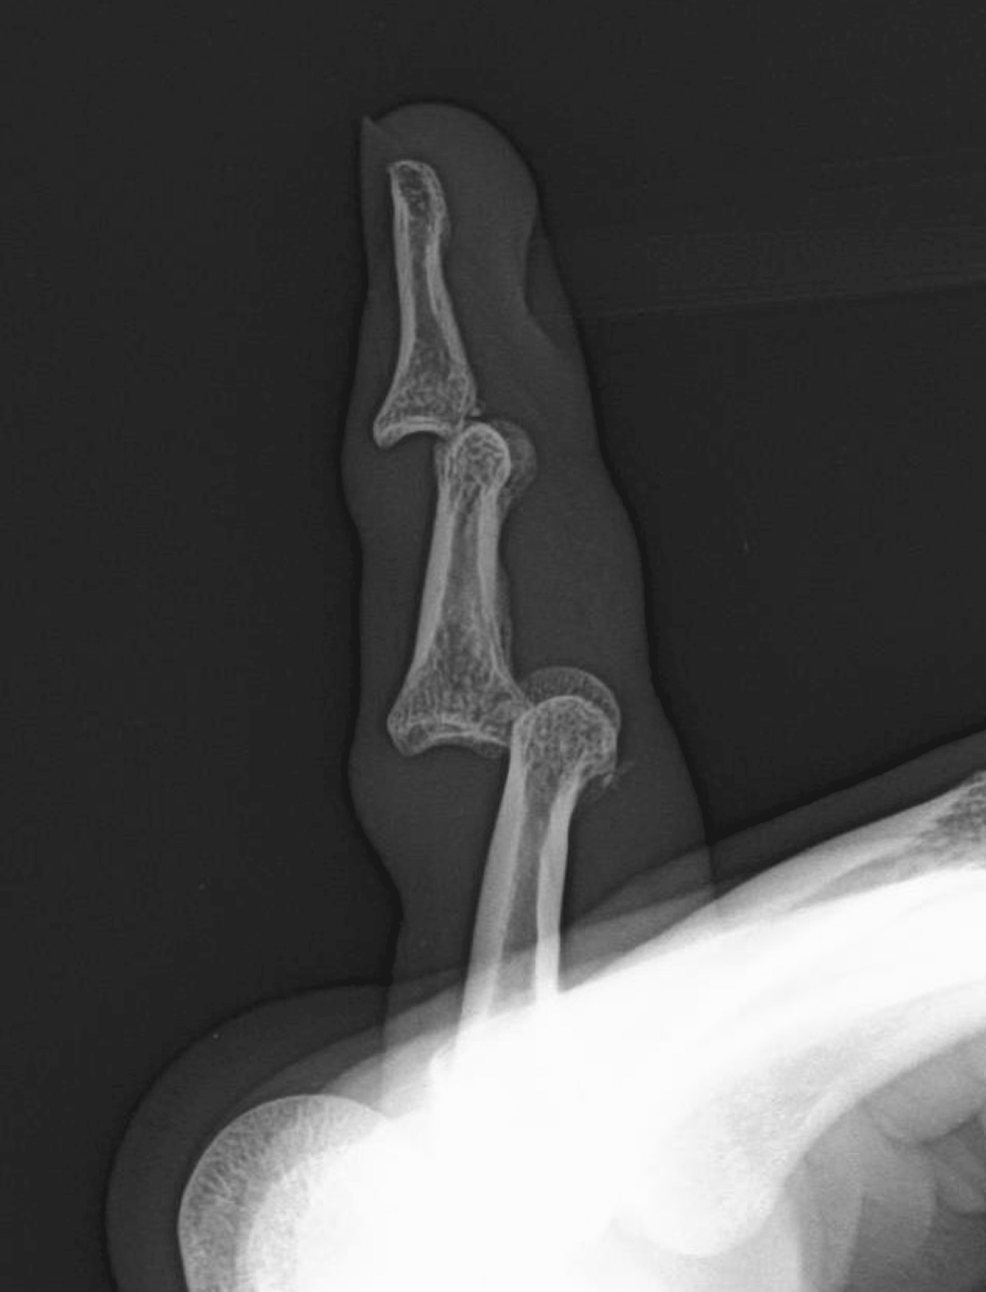

Thumb distal interphalangeal joint (DIP) dislocation real case study Thumb Dip Joint Dislocation Thumb cmc dislocations are rare injuries that occur due to axial force on a flexed thumb. The metacarpophalangeal (mcp) joint most commonly dislocated is that of the thumb. Dislocations of this joint can be very problematic. A simple dislocation involves no soft tissue obstruction, and. Simple closed dip joint dislocations can be mobilized early and should get a good outcome. Thumb Dip Joint Dislocation.

Radiology case Dislocation of interphalangeal joint of thumb Thumb Dip Joint Dislocation Dislocations of this joint can be very problematic. Finger dislocation can occur at the proximal interphalangeal (pip), distal interphalangeal (dip), or metacarpophalangeal (mcp) joints. Finger dislocation is a common hand injury that can occur at the proximal interphalangeal (pip), distal interphalangeal (dip), or metacarpophalangeal (mcp) joints and can also occur in the dorsal, volar, or lateral planes. Simple closed dip. Thumb Dip Joint Dislocation.

Dislocation of Thumb (XRay) radRounds Radiology Network Thumb Dip Joint Dislocation Diagnosis is clinical and can be confirmed by orthogonal radiographs. A simple dislocation involves no soft tissue obstruction, and. Finger dislocation can occur at the proximal interphalangeal (pip), distal interphalangeal (dip), or metacarpophalangeal (mcp) joints. Phalanx dislocations are common traumatic injury of the hand involving the proximal interphalangeal joint (pip) or distal interphalangeal joint. The proximal interphalangeal (pip) joint is. Thumb Dip Joint Dislocation.